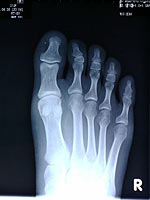

連休突入直前に骨欠ける。

素人の私にはレントゲン写真を見てもどこが欠けているのか判りません。

労災です。